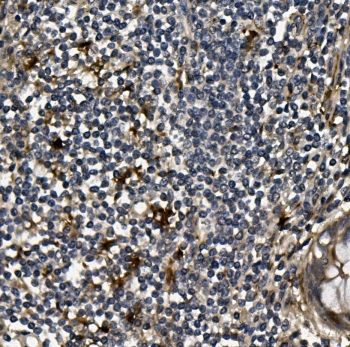

IHC staining of FFPE human rectal cancer with VEGF antibody. HIER: boil tissue sections in pH6, 10mM citrate buffer, for 20 min and allow to cool before testing.